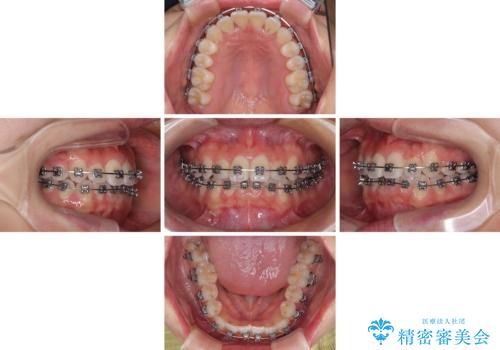

- 矯正装置

- メタルブラケット

装置の外見を気にしていましたが、短期間で治療を終えることができるだろうと伝えると、安価であるメタルブラケットを選択されました。